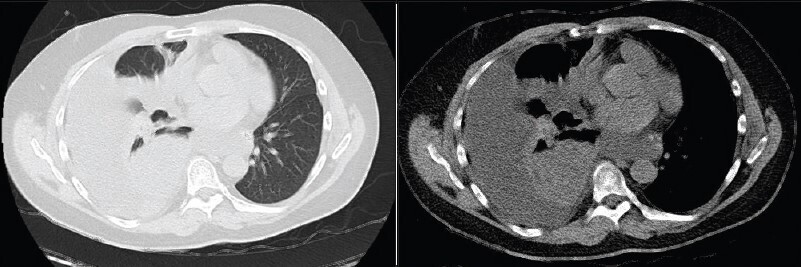

Vous n’observez pas de signe de lutte respiratoire, la dyspnée est silencieuse. L’auscultation pulmonaire retrouve une diminution du murmure vésiculaire à droite, accompagnée de sibilants localisés à mi-hauteur, la percussion révèle une matité. Les bruits du cœur sont réguliers, sans souffle. Il n’y a pas d’œdème des membres inférieurs, les mollets sont souples et indolores. Le reste de l’examen clinique est sans particularité.

Le tableau clinique n’est pas évocateur d’un asthme : les sibilants sont localisés et non diffus, la dyspnée n’est pas bruyante, ni limitée au temps expiratoire. De plus, un asthme aigu grave se définit par un peak flow < 150 L/min ou < 50 % de la théorique, ce qui n’est pas le cas ici. Les sibilants peuvent être le signe d’une obstruction bronchique localisée.